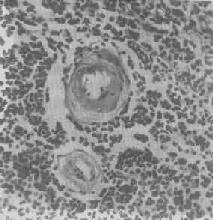

脾中央动脉玻璃样变

图1-20 脾中央动脉玻璃样变

中央动脉管壁明显增厚,呈玻璃样均质状,管腔变窄

肾近曲小管上皮细胞玻璃样小滴变

图1-21 肾近曲小管上皮细胞玻璃样小滴变

上皮细胞胞浆内出现大小不等的均质圆形小滴